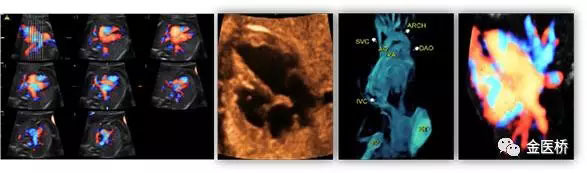

胎兒心臟超聲又名胎兒超聲心動(dòng)圖,是一種無(wú)創(chuàng)、安全的影像學(xué)檢查,也是胎兒期唯一有效的能夠顯示胎兒心臟結(jié)構(gòu)、血流及評(píng)估心臟功能的影像學(xué)手段,在產(chǎn)前及時(shí)診斷,隨診,預(yù)后判斷至關(guān)重要,不可替代。

一般情況下,一個(gè)詳細(xì)完整的胎兒心臟彩超檢查大約需要30-60分鐘。